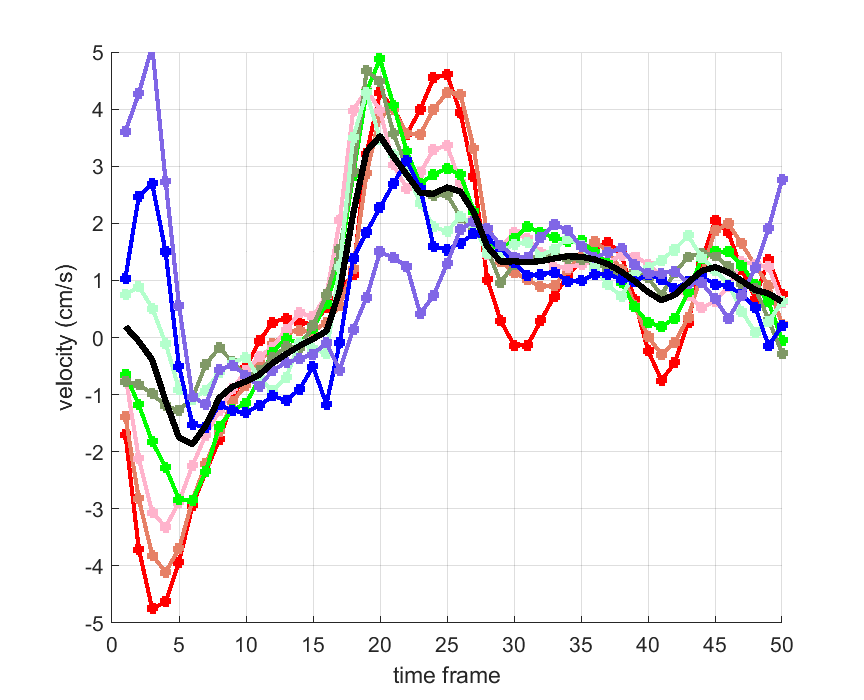

Time courses of the estimated translational component per subject, frame, slice and volume along the 3 velocity directions x, y and z are presented in Fig.6 - Fig.8.